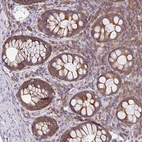

Immunohistochemical staining of human rectum shows strong cytoplasmic positivity in glandular cells.